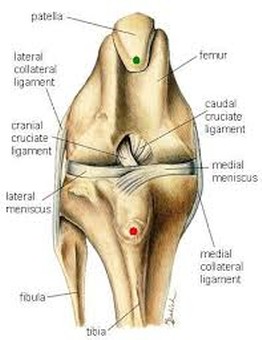

La stabilità dell’articolazione del ginocchio è dovuta anche ai legamenti crociati, che ne regolano i movimenti, prevenendo lo slittamento craniale o caudale della tibia sul femore, limitando la rotazione interna della tibia sul femore e opponendosi all’iperestensione del ginocchio.

La rottura del legamento crociato craniale è la più comune lesione del ginocchio del cane. Tale rottura può essere totale o parziale; quest’ultima si può verificare a carico della sola banda cranio-mediale, durante la flessione del ginocchio, soprattutto se accompagnata da rotazione interna, o a carico della banda caudo-laterale, durante l’iperestensione dell’articolazione.

Qualunque sia la causa, dalla rottura del legamento crociato craniale deriva una instabilità persistente dell’articolazione del ginocchio, che determina infiammazione della capsula articolare e della membrana sinoviale, degenerazione della cartilagine articolare, produzione di osteofiti periarticolari e danni ai menischi sopratutto il menisco mediale.